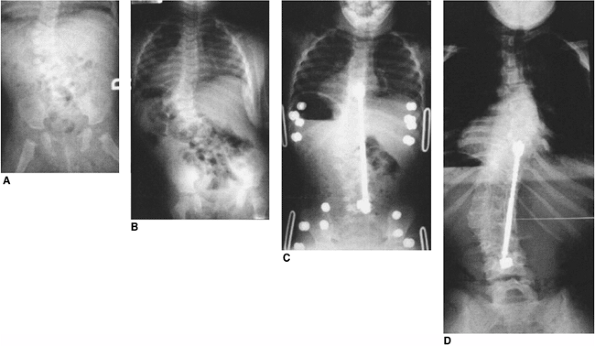

Figure 19.2 Anomalies associated with congenital scoliosis. A:

One-week-old infant with congenital scoliosis. The multiple vertebral anomalies seen here include vertebral bony bars, hemivertebrae, and wedge vertebrae. Other anomalies included ear anomalies and deafness, solitary kidney, imperforate anus, tethered spinal cord, atrial septal defect, hypoplastic lung, and radial hypoplasia. B: Three-dimensional computed tomography (CT) scan of the same patient at 10 months. Fused ribs on the concavity of the thoracic scoliosis will act as a tether, producing more deformity with growth. C: Upright radiograph at 10 months. A new curvature in the more normal thoracolumbar spine is compensatory to the upright position, but should suggest the possibility of spinal cord tethering. D: Cutaneous abnormalities such as this skin dimple over the thoracolumbar spine may indicate an underlying intraspinal anomaly. |

Figure 19.10

This two-and-a-half-year-old patient with vertebrae-anus-cardiovascular-trachea-esophagus-renal-limb-buds (VACTERL) syndrome underwent in situ fusion of progressive congenital thoracic scoliosis associated with concave fused ribs at 14 months of age. A: At 2½ thoracic curve progression has continued postoperatively. B: One year postoperatively, after expansion thoracostomies at two levels, insertion of rib-to-rib and rib-to-spine devices, and device lengthening. C: Three years postoperatively after vertical expandable prosthetic titanium rib (VEPTR) devices were outgrown and replaced with longer devices. |